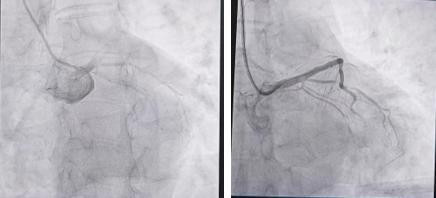

极目新闻通信员胡梦黎婉婷 急性心梗发病急、不吉高,一朝延误救治极易危及人命。近日,家住葛店的赵先生因突发急性心肌梗死伴心源性休克,两度人命弥留,所幸经湖北省中病院(湖北中医药大学附庸病院)葛店院区心内科医护团队全力抢救,最终药到回春。群众领导,急性心梗发作前形体会发出多项求救信号,忽视拖延可能形成大祸。 59岁的赵先生平常形体十分健康,因此在突发胸闷不适后,他硬扛了2小时,直到胸闷愈发剧烈,才伏击前去下层卫生中心就诊,被初步会诊为急性冠脉空洞征。在调整历程中赵先生一忽儿昏倒、意志丧失,医护东谈主员立即展抖擞肺复苏、电除颤,经过10分钟的伏击抢救,他的意志才凑合还原。飞快被伏击送往湖北省中病院葛店院区急诊科。 经过一系列搜检,急诊科大夫判断赵先生是急性侧壁+前间壁+前壁心肌梗死、心源性休克,于是立即关联心内科副主任医师陈晨,准备急诊手术。此时的赵先生已处于心源性休克情景,病情不吉。急诊冠脉造影效果线路,他的左骨干血管终局绝对封闭,高出于腹黑的主供血管被透顶堵死,还磨灭有心房震憾。“前降支封闭导致的大面积前壁心肌梗死,磨灭新发房颤后,心源性休克、恶性心律失常以致暴毙的风险会成倍加多。”陈晨示意。 赵先生的救治历程远比念念象中转折。首根导丝尝试屡次均未能通过封闭病变,最终在微导管提拔下穿过封闭部位。但急性血栓堵塞了血管,球囊彭胀后血管仍无血流通过,陈晨立即接管戳破球囊冠脉内给药、血栓抽吸等一系列操作,终于看到远端血管显影,随后在前降支近段植入支架,复查线路所有这个词血管血流畅通,第一步援助宣告收效。

左边为救治前的血管造影,右边为救治后的血管造影 术后赵先生转入病房,胸闷症状仍未绝对缓解,心源性休克情景抓续,恶性心律失常的风险也曾居高不下。葛店心内科医护团队全程信守,24小时密切监测。术后第一天夜晚,赵先生突发恶性心律失常,主治大夫田罗立即组织医护团队张开抢救,经过伏击措置,赵先生药到回春,胸闷症状也彰着缓解。这场与死神的较量,医护团队再胜一局。 经过多天的用心调整,赵先生的形体逐渐康复,顺利出院。出院本日,家属稀奇送来锦旗,向陈晨磨真金不怕火及葛店心内科整体医护东谈主员抒发最诚挚的感谢。 陈晨磨真金不怕火领导,急性心肌梗死并非“毫无征兆”,大广漠患者在梗死发生前的数小时、数天以致数周,形体皆会发出预警信号: 1.胸闷、胸痛:这是最常见的信号,多发达为胸部压榨样、紧缩样痛苦,可能抓续数分钟,休息后无法缓解,部分东谈主还会辐射到左肩、后背、颈部或下巴; 2.心慌、心悸:嗅觉心跳不功令、过快或过慢,伴有头晕、乏力,以致目前发黑; 3.非典型症状:部分东谈主不会出现彰着胸痛,而是发达为不解原因的呼吸贫瘠、恶心吐逆、大汗淋漓、抓续疲困,好像上腹不适、牙痛、下颌痛等,这类“荫藏信号”更易被忽视; 陈晨磨真金不怕火强调,一朝出现上述任何一组症状,尤其是抓续胸痛跨越15分钟或伴有大汗、濒死感,立即罢手所有动作,保抓欢然,接管半卧位(若呼吸贫瘠)或横卧(若血压低),独立即拨打急救电话,不冷落自行驾车就医(会昏倒)。既往确诊冠心病者可含服硝酸甘油,需恭候专科急救。同期,中老年东谈主尤其是有基础病史的东谈主群,要如期体检,养成低盐低脂饮食、功令通顺、戒烟限酒的好民俗,从源泉上镌汰心梗风险。 |